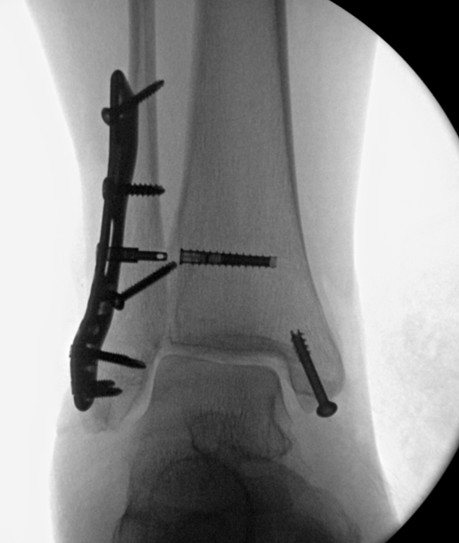

تشرفت بالمشاركة في مؤتمر Egypt Intensive Advanced Professional Limb Reconstruction (EAPLR) الذي أُقيم في الأقصر 2-3 April

استعرض المؤتمر تاريخ وتطورات جراحات تطويل وإعادة بناء الأطراف.